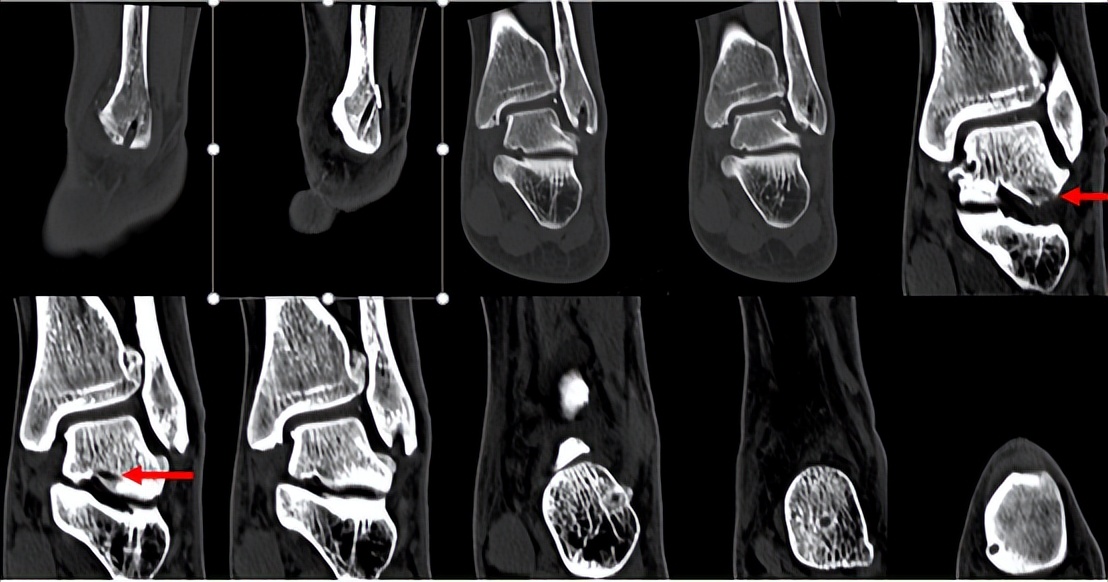

林先生来到省二医后,何河北医生为其进行了详细查体,检查后确诊为踝关节不稳+滑膜软骨瘤。

何河北制定了详细的手术方案,为患者开展踝关节镜下滑膜软骨瘤取出术+距腓前韧带重建术。他从患者踝关节中取出32颗“珍珠”(关节游离体),然后进行踝关节外侧韧带重建。

▲术前可见踝关节前方有大量“珍珠”。

▲术中取出31颗滑膜软骨瘤。

▲术后CT显示滑膜软骨瘤完全取出,韧带重建良好。